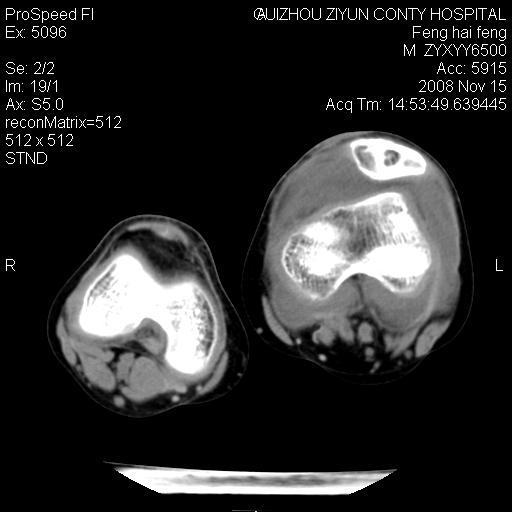

标题: CT16656:M 14Y 左膝关节肿胀一年余。其余病史不详。 [打印本页]

标题: CT16656:M 14Y 左膝关节肿胀一年余。其余病史不详。

考虑左侧髌骨结核;左膝关节滑膜肿胀、增厚,关节囊积液。

左膝滑膜型关节结核可能性大!支持!滑膜型关节结核主要ct表现:关节囊肿胀,积液,关节面见小破坏灶,并见点状死骨!

左膝滑膜型关节结核可能性大!支持!滑膜型关节结核主要ct表现:关节囊肿胀,积液,关节面见小破坏灶,并见点状死骨

好大的左腿!考虑左侧髌骨结核,左膝关节滑膜肿胀、增厚,关节囊积液。

左侧髌骨结核;左膝关节滑膜肿胀、增厚,关节囊积液